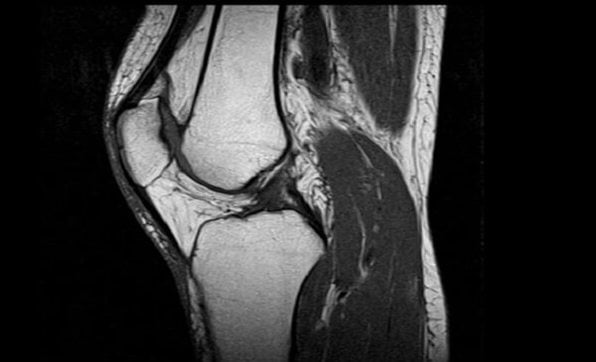

Магнитно-резонансная томография

Еще один камень преткновения – что лучше, МРТ или УЗИ коленного сустава. Разберемся с МРТ на понятийном уровне.

Магнитно-резонансная томография основана на использовании волн магнитной и радио-природы (из короткого диапазона). Томограф создает магнитное поле, которое формирует из протонов водородных атомов пучок радиоволн. Под его воздействием протоны молекул тканей нашего организма генерируют «ответный» сигнал. Он принимается другим узлом томографа, передается на подсоединенный компьютер и переводится им в графическое изображение исследуемых структур.

С другой стороны, на проведении МРТ нередко настаивают сами пациенты, уверенные в том, что более точной методики диагностики не существует. Сами врачи точно знают, что магнитно-резонансная томография нужна лишь в предоперационном периоде, когда требуется уточнение локализации ранее установленной патологии. Обычно в ней есть нужда после травм или при обнаружении новообразований.

Если обнаружено заболевание коленного сустава, но не установлена ни протяженность патологии, ни его конкретная локализация, ни степень васкуляризации (появления новых, «не запланированных» природой сосудов), никакого диагностического преимущества МРТ не обеспечивает. Тот же гонартроз, осложненный вторичным синовитом, диагностируется обычным УЗИ, причем со всеми подробностями. А обходится исследование значительно дешевле – за проведение МРТ меньше 3,5 тысяч рублей с вас не возьмут даже в самой бюджетной клинике.